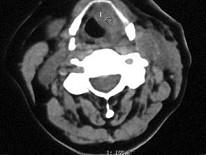

女,54岁,鼻咽部异物感约3个月,PE:左侧声带固定,可见肿物,CT如图所示,应诊断为 ( )

鼻咽癌( )